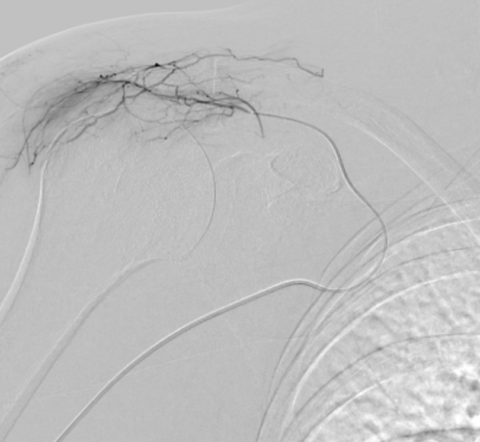

Grâce à l’imagerie de précision (angiographie), le radiologue interventionnel identifie ces vaisseaux « anormaux » et les occlut sélectivement. En bloquant leur flux sanguin, on réduit l’apport en oxygène et nutriments à la zone enflammée, favorisant une régénération rapide des symptômes.

Guidage par imagerie : Le cathéter est avancé jusqu’à l’artère sous-clavière sous contrôle radioscopique en temps réel.

Injection ciblée : Lipiodol dilué dans du produit de contraste iodé est injecté pour boucher les artères pathologiques.

Vérification : Angiographie de contrôle pour confirmer le succès.